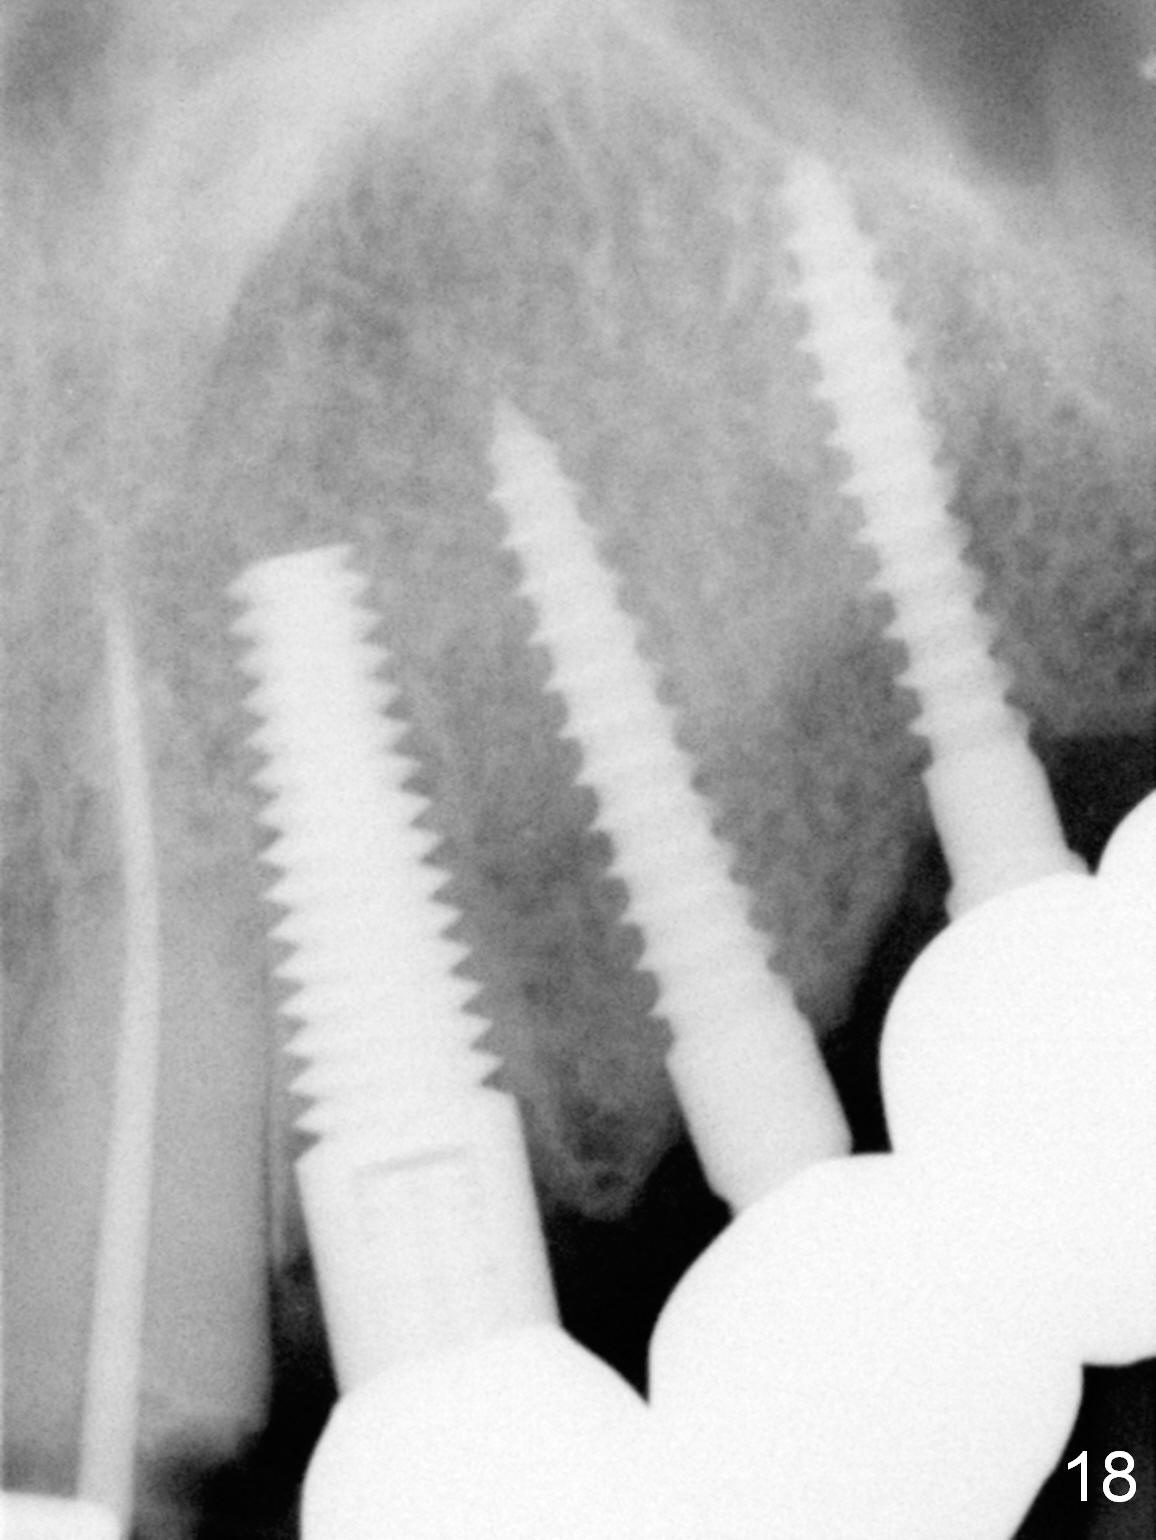

Six months post cementation, the tooth #9 becomes symptomatic.  Is it possible that the implant at #10 is too close to the root of #9?  It is asymptomatic after pulpotomy, but the tooth fractures equi/supragingivally.  Two PAs taken while RCT show osteointegration at #10-12 (Fig.18,19).  While the bone density increases at #10 regular implant, there is minimal bone loss around the 1-piece implants 13 months post cementation (18 months postop, Fig.20,21).  The gingiva remains healthy 19 months post cementation (Fig.22).  76岁病人突然打电话说一个植牙牙冠松动,其实9号牙(自然牙)折裂,6,10-13号牙植牙好像没有骨质吸收(图二十三至二十五),10-13牙位牙龈健康(图二十六,行使功能五年)。9号牙牙冠重新粘固后,显示前牙深覆合,深覆盖(图二十七,二十八)。如果再次脱落需要植牙,选择一段式有助于植入和修复,因为植体和基台直径小。两段式植牙相对基台直径至少4,或者4.5毫米,前牙修复显得笨重。由于9,10牙根和植体接近,9号牙植体需要偏小而长,3x14或者15毫米(图二十九)。